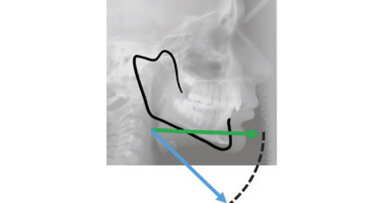

Although Class III elastics tend to extrude the maxillary molars and generate clockwise mandibular rotation, aligners allow us to prevent these complications, since we have better control over tooth movement, enabling us to counteract unwanted dental movements. In this case, an intrusion of the posterior teeth was planned, which would generate anticlockwise rotation of the mandible in an anticlockwise direction. This vertical control led to the closure of the anterior open bite and the reduction of the lower facial height, thereby improving the facial profile.